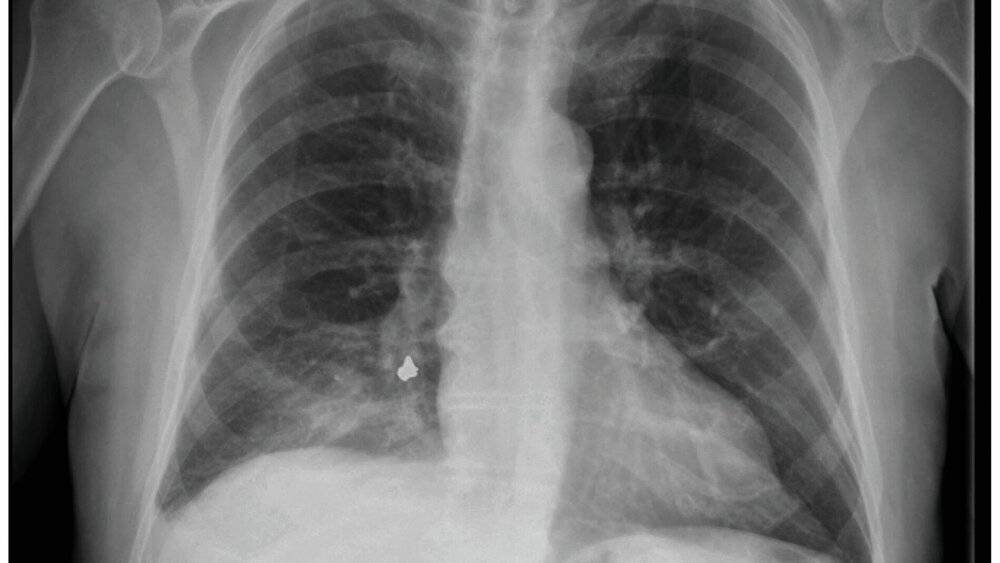

Der 93-jährige Patient stellte sich in der Notaufnahme in reduziertem Allgemeinzustand, Husten und Kurzatmigkeit vor. Seit Symptombeginn vier Tage zuvor hatte sich der Zustand des Patienten trotz Antibiotika-Therapie verschlechtert. In der Röntgenaufnahme des Thorax zeigte sich im infrahilären Bereich eine Verschattung, die den Verdacht auf einen Fremdkörper bestätigte. Zur genaueren Lokalisation wurde ein CT des Brustkorbs angefertigt. Der Fremdkörper wurde im subsegmentalen Bronchus im hinteren, rechten Unterlappen lokalisiert. Des Weiteren zeigte sich eine distale Konsolidierung, die mit einer postobstruktiven Pneumonie vereinbar war. Der Fremdkörper wurde anschließend mittels Bronchoskopie entfernt. Es handelte sich um eine Zahnkrone aus einer Goldlegierung mit umliegendem, purulentem Schleimmaterial. Der Patient konnte unter Antibiose bereits am Folgetag entlassen werden.